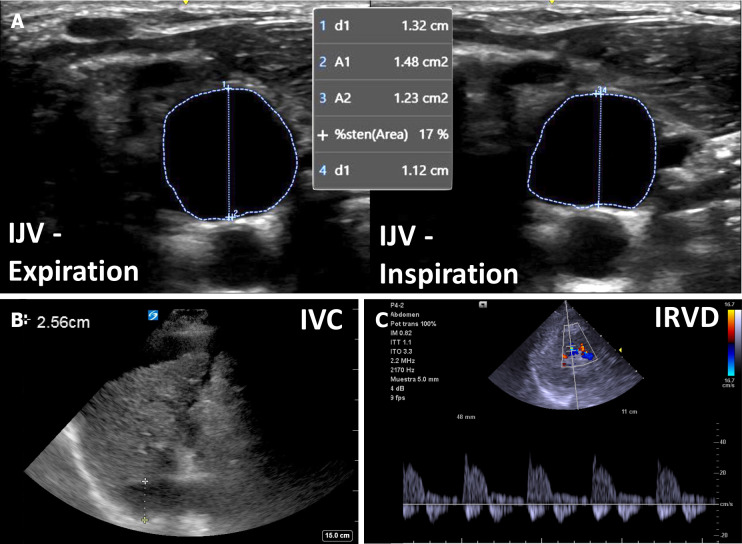

This article delves into the intricate challenges of acute kidney injury (AKI) in cirrhosis, a condition fraught with high morbidity and mortality. The complexities arise from distinguishing between various causes of AKI, particularly hemodynamic AKI, in cirrhotic patients, who experience hemodynamic changes due to portal hypertension. The term "hepatocardiorenal syndrome" is introduced to encapsulate the intricate interplay among the liver, heart, and kidneys. The narrative emphasizes the often-overlooked aspect of cardiac function in AKI assessments in cirrhosis, unveiling the prevalence of cirrhotic cardiomyopathy marked by impaired diastolic function. The conventional empiric approach involving volume expansion and vasopressors for hepatorenal syndrome is critically analyzed, highlighting potential risks and variable patient responses. We advocate for a nuanced algorithm for AKI evaluation in cirrhosis, prominently featuring point-of-care ultrasonography (POCUS). POCUS applications encompass assessing fluid tolerance, detecting venous congestion, and evaluating cardiac function.